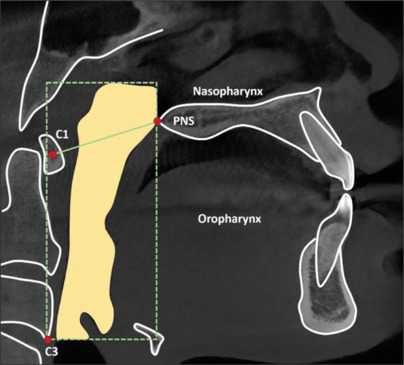

Material and methods: A cross-sectional descriptive prospective study analysis was conducted on 120 patients with varying skeletal patterns who sought examination and treatment at the Department of Dentistry and Maxillofacial Surgery, Can Tho University of Medicine and Pharmacy Hospital. Imaging data from these patients were used to evaluate the volume of the tongue and pharyngeal airway in adults with different malocclusion conditions.

Results: The average volumes of TV (Tongue volume) and TPV (Total pharynx volume) in Class III malocclusion were the largest, with values of 57820.86 cm3 and 28385.33 cm3, respectively. In contrast, the smallest volumes were observed in Class II, with values of 50380.48 cm3 and 23414.58 cm3, respectively.

Conclusions: An inverse correlation has been established between the TV/OCV (Tongue volume/Oral cavity volume) ratio and pharyngeal airway volume. This finding suggests that tongue volume, oral cavity volume, and their ratio influence airway patency. Understanding the relationship between the tongue and the airway in orthodontic treatment planning, particularly in improving airway space for patients with Class II malocclusion.